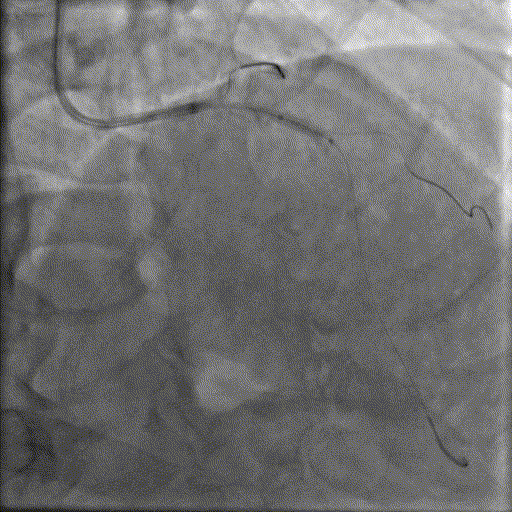

手术经过

导丝到位

当指引导管冠脉开口到位后,选择三根对应导丝分别送入LAD、D1、D2远端。

球囊预扩

选择不同尺寸的预扩球囊逐级预扩张病变,复查造影狭窄减轻不明显。为了解血管真实情况,遂启用IVUS检查。

术前腔内影像学IVUS指导

IVUS提示血管内钙化严重,最小管腔面积不足 4mm²;遂考虑启动IVL治疗。

冲击波球囊治疗

2.5*12mm@4atm 冠脉血管内冲击波导管反复进行8个周期治疗,经IVUS检查提示最小管腔面积增加至4.88mm²;随后选取后扩张球囊对病变行扩张治疗。

支架植入并后扩

于LM-LAD依次植入两枚药物洗脱支架,经非顺应性球囊后扩张支架,复查造影&IVUS提示血管内钙化仍较重,支架贴壁不良,遂再次启动IVL治疗。